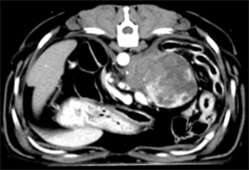

病名:褐色細胞腫 手術法:右副腎腫瘍摘出術

症例:9歳 Mix犬 避妊雌

主訴:1ヶ月前から急に元気がなくなり、失神することもあるとのことでかかりつけの病院で診察をうけ、検査にて腹腔内に腫瘍があるとのことでご紹介を受け当病院に来院されました。

腹部超音波検査およびCT検査にて右副腎に直径6cm大の腫瘍(赤矢印)が認められました。機能性副腎腫瘍が疑われ、飼い主様の希望により摘出手術を行いました。